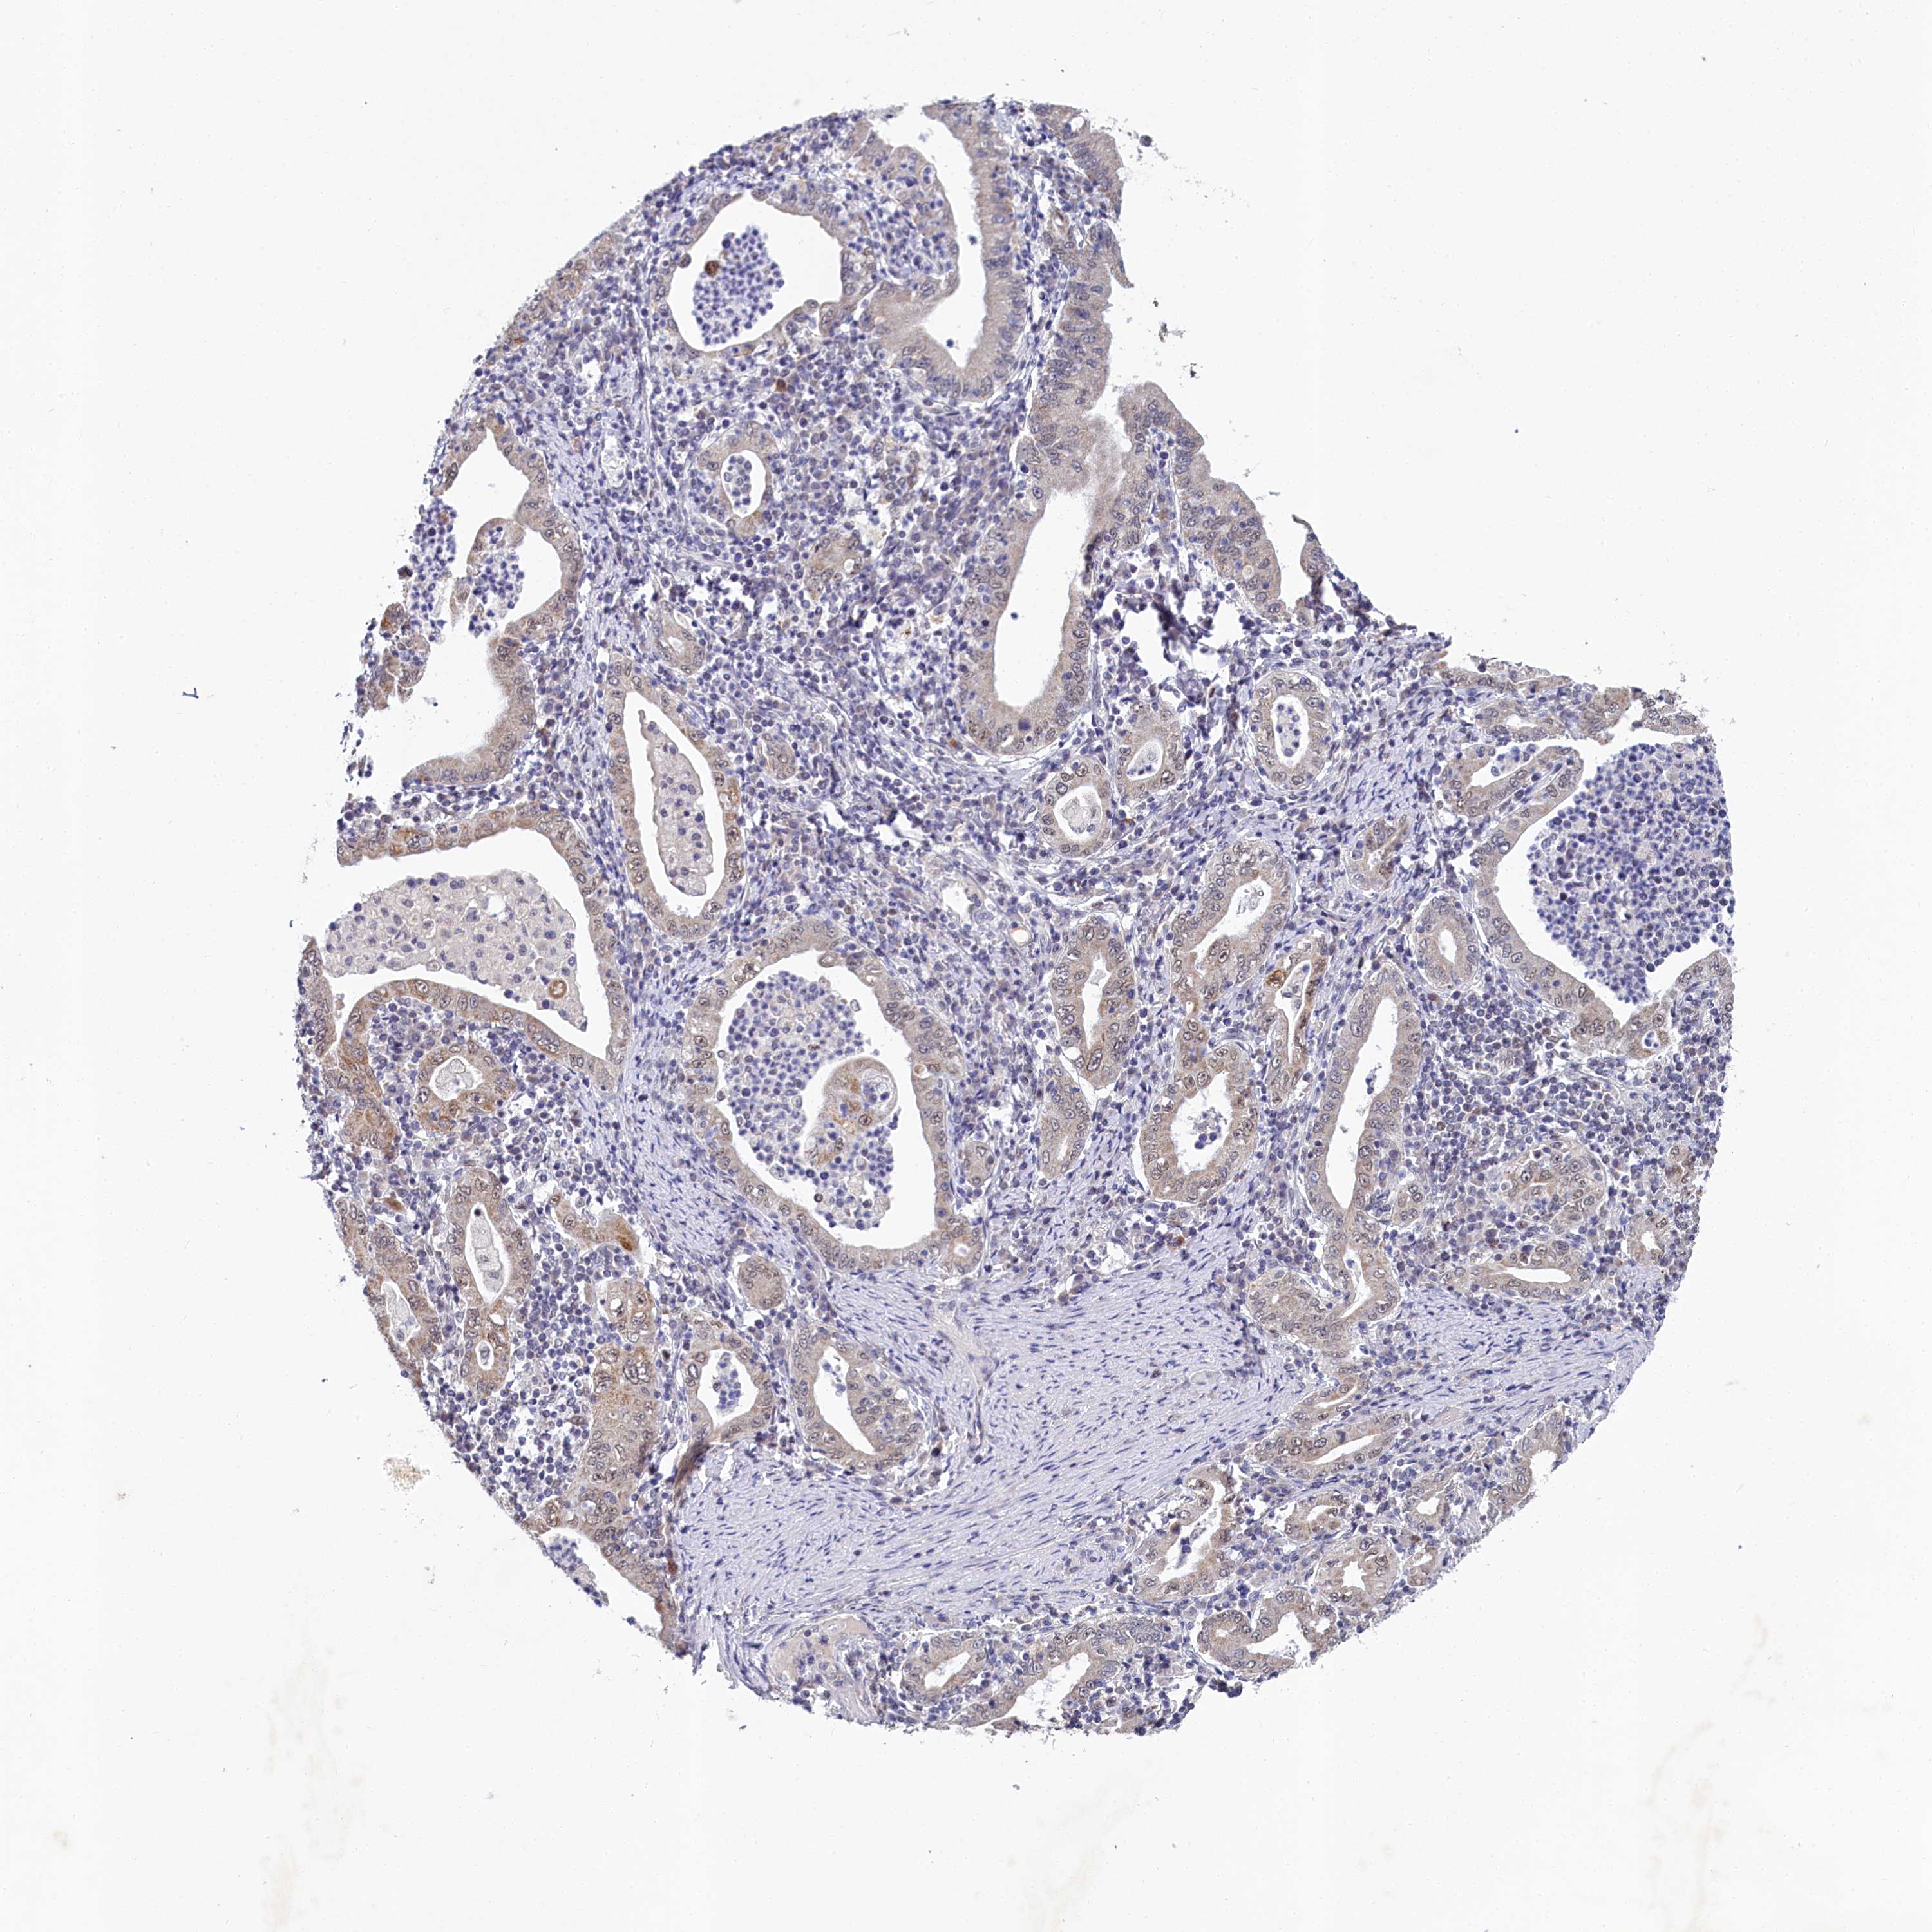

STOMACH CANCER - Protein expressioni

A mouse-over function shows sample information and annotation data. Click on an image to view it in a full screen mode. Samples can be filtered based on level of antibody staining by selecting one or several of the following categories: high, medium, low and not detected. The assay and annotation is described here.

Note that samples used for immunohistochemistry by the Human Protein Atlas do not correspond to samples in the TCGA dataset.

Antibody stainingi

Antibody staining in the annotated cell types in the current human tissue is reported as not detected, low, medium, or high, based on conventional immunohistochemistry profiling in selected tissues. This score is based on the combination of the staining intensity and fraction of stained cells.

Each image is clickable and will lead to virtual microscopy that enables deeper exploration of all samples and also displays staining intensity scores, fraction scores and subcellular localization as well as patient and tissue information for each sample.

Antibody HPA038902

Antibody HPA038903

Staining

High

Medium

Low

Not detected

Intensity

Strong

Moderate

Weak

Negative

Quantity

>75%

75%-25%

<25%

None

Location

Nuclear

Cytoplasmic/membranous

Cytoplasmic/membranous,nuclear

Adenocarcinoma, NOS

Adenocarcinoma, High grade